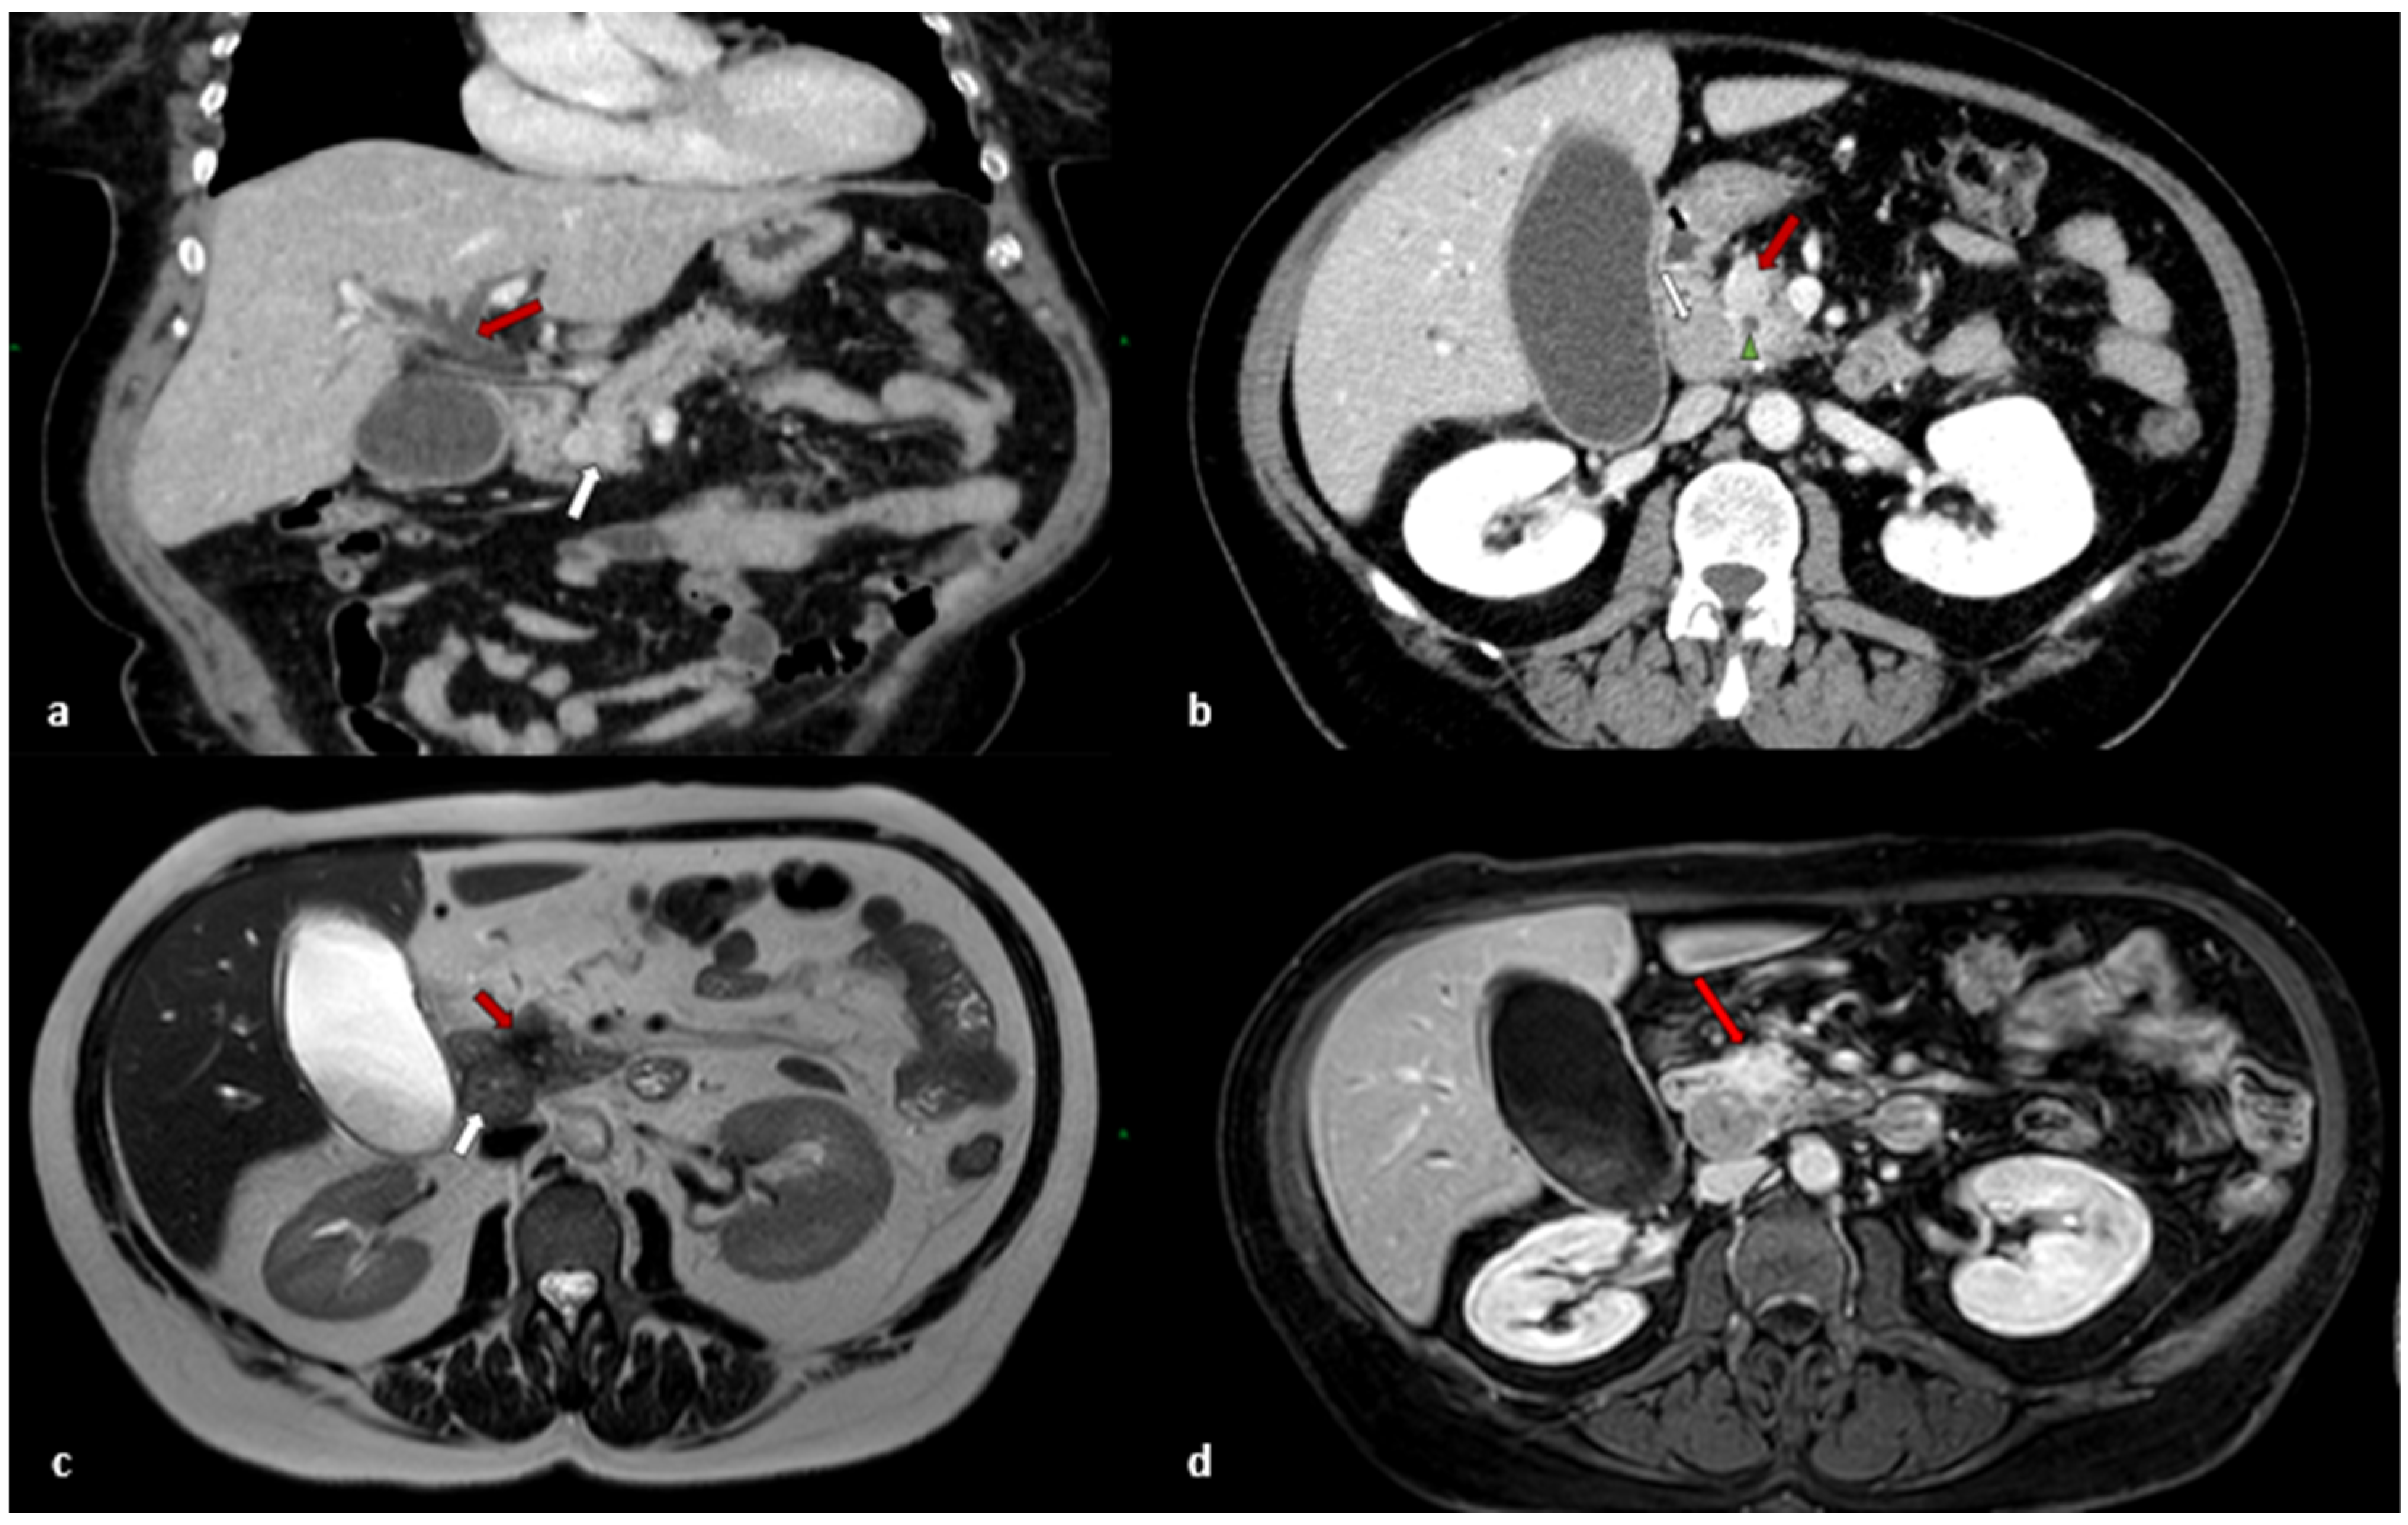

2. Case Report

2.1. Clinical Presentation

2.2. Treatment

2.3. Histological Findings

2.4. Outcomes and Follow-Up